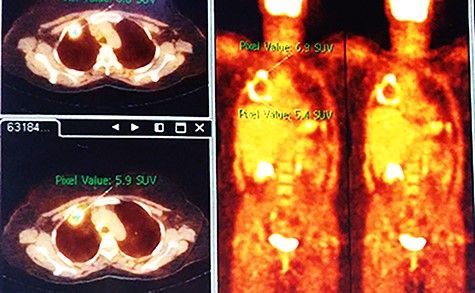

Chest X-ray (CXR) showed a heterogeneous density with irregular margins in the right lung (Fig. 1). CT scan demonstrated a heterogeneous mass that measured 5.5 × 6 × 7.8 cm with irregular thick margins. The mass was anteriorly located in the upper lobe of the right lung with air bubbles and necrosis (Fig. 2). Two lymphadenopathies were observed that measured around 2 cm each; one of which was in the hilum of the right lung and the other was located inferior to the right main bronchus. No other lesion was detected elsewhere. PET scan was also suggestive of malignancy as it demonstrated a heterogeneous mass with irregular margins which had irregular enhancement in the peripheral, suggesting hyper metabolic retention. The standardized uptake values (SUV) of the mass ranged between 4 and 7 with central necrosis and multiple gas bubbles. Multiple lymphadenopathies were also observed with different sizes ranged from 10 to 20 mm with SUVmax reaching 7 (Fig. 3). Bronchoscopy found an erythematous and oedematous opening of the anterior segment of the right upper lobe of the lung and epithelial dysplasia was found with bronchial lavage (BAL), but endobrachial biopsy was not conclusive.

When using PET-scan, lesions that demonstrate Fludeoxyglucose (FDG) retention and have SUVmax higher than 2.5–3 are approached as malignancies [6]. However, results that are false positives are expected as many conditions can cause FDG retention and enhancement such as granulomatosis, inflammation and infection, with tuberculosis, sarcoidosis and parasite diseases being among the most common causes [7]. One study had 15 cases of hydatid cysts which mimicked malignancies on PET-scan and was speculated that local inflammation by the ruptured cyst was the reason for the resemblance [4]. In our case, the cyst ruptured and had infection, which can explain the resemblance of malignancy on PET scan. In another study, the quite opposite to our case was observed; a lung carcinoma mimicked hydatid cyst with positive serology for echinococcus granulosus, which can further confirm the resemblance that can occur [8]. FNA should be avoided in hydatid cysts to avoid rupture and anaphylaxis in the patient, which is why they should be excluded before any procedure even in cases of apparent malignancy. FNA was conducted in our case as malignancy was suspected, not echinococcus granulosus. PET scan is an expensive imaging and therefore test for echinococcus granulosus should have been conducted before, particularly that in Syria financial burden can limit in some extent medical treatment in some cases [9].